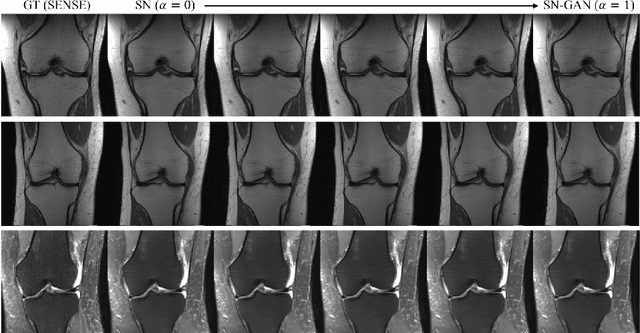

Abstract:We present a deep network interpolation strategy for accelerated parallel MR image reconstruction. In particular, we examine the network interpolation in parameter space between a source model that is formulated in an unrolled scheme with L1 and SSIM losses and its counterpart that is trained with an adversarial loss. We show that by interpolating between the two different models of the same network structure, the new interpolated network can model a trade-off between perceptual quality and fidelity.

Abstract:Purpose: To systematically investigate the influence of various data consistency layers, (semi-)supervised learning and ensembling strategies, defined in a $\Sigma$-net, for accelerated parallel MR image reconstruction using deep learning. Theory and Methods: MR image reconstruction is formulated as learned unrolled optimization scheme with a Down-Up network as regularization and varying data consistency layers. The different architectures are split into sensitivity networks, which rely on explicit coil sensitivity maps, and parallel coil networks, which learn the combination of coils implicitly. Different content and adversarial losses, a semi-supervised fine-tuning scheme and model ensembling are investigated. Results: Evaluated on the fastMRI multicoil validation set, architectures involving raw k-space data outperform image enhancement methods significantly. Semi-supervised fine-tuning adapts to new k-space data and provides, together with reconstructions based on adversarial training, the visually most appealing results although quantitative quality metrics are reduced. The $\Sigma$-net ensembles the benefits from different models and achieves similar scores compared to the single state-of-the-art approaches. Conclusion: This work provides an open-source framework to perform a systematic wide-range comparison of state-of-the-art reconstruction approaches for parallel MR image reconstruction on the fastMRI knee dataset and explores the importance of data consistency. A suitable trade-off between perceptual image quality and quantitative scores are achieved with the ensembled $\Sigma$-net.

Abstract:We explore an ensembled $\Sigma$-net for fast parallel MR imaging, including parallel coil networks, which perform implicit coil weighting, and sensitivity networks, involving explicit sensitivity maps. The networks in $\Sigma$-net are trained in a supervised way, including content and GAN losses, and with various ways of data consistency, i.e., proximal mappings, gradient descent and variable splitting. A semi-supervised finetuning scheme allows us to adapt to the k-space data at test time, which, however, decreases the quantitative metrics, although generating the visually most textured and sharp images. For this challenge, we focused on robust and high SSIM scores, which we achieved by ensembling all models to a $\Sigma$-net.